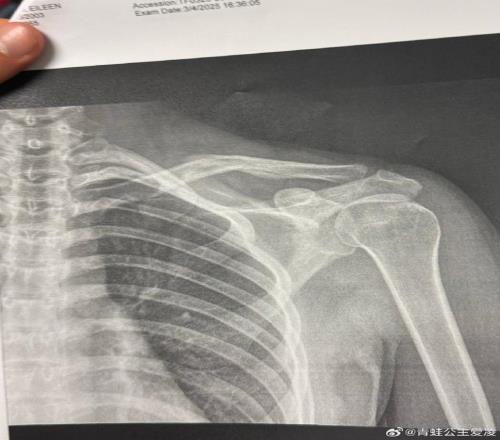

2025年3月9日,谷愛凌在社交網(wǎng)絡(luò)上發(fā)布了一張X光片。

但事實(shí)是,谷愛凌確實(shí)在這個(gè)奧運(yùn)周期的最后沖刺階段不停經(jīng)歷著傷病的折磨。2025年3月9日,谷愛凌在社交網(wǎng)絡(luò)上發(fā)布了一張X光片。圖片上,她右側(cè)鎖骨的裂縫清晰可見,配文只有一個(gè)心碎的表情符號(hào),而這僅僅是“職業(yè)生涯最艱難一年”的開始。